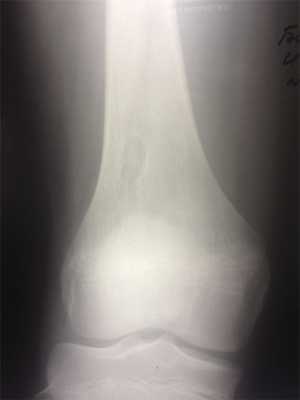

При рентгенологическом исследовании МФД выглядит как округлое или овальной формы литическое образование кортикального слоя (или субпериостально), чаще немного вытянутое параллельно оси кости. Границы четкие, как правило, хорошо заметна небольшая зона остеосклероза вокруг (рис. 3). По мере роста МФД начинает распространяться в медуллярном направлении. Поэтому НОФ всегда выглядит эксцентрично, но также с четкими границами и зоной перифокальных остеосклеротических изменений (рис. 4). При больших поражениях, занимающих более трети—половины поперечника кости, часто можно обнаружить дольчатость за счет склерозированных септ, в составе которых при гистологическом исследовании определяется фиброзная ткань с очагами реактивного остеогенеза. В данных случаях заболевание может манифестировать патологическим переломом. В редких случаях контуры НОФ могут выходить за анатомические пределы кости. Периостальная реакция в большинстве случаев отсутствует.

Рис. 3. Хорошо ограниченный кортикальный очаг поражения в зоне дистального метафиза бедренной кости. Перифокальные склеротические изменения не выражены. Стадия, А по Ritschl.